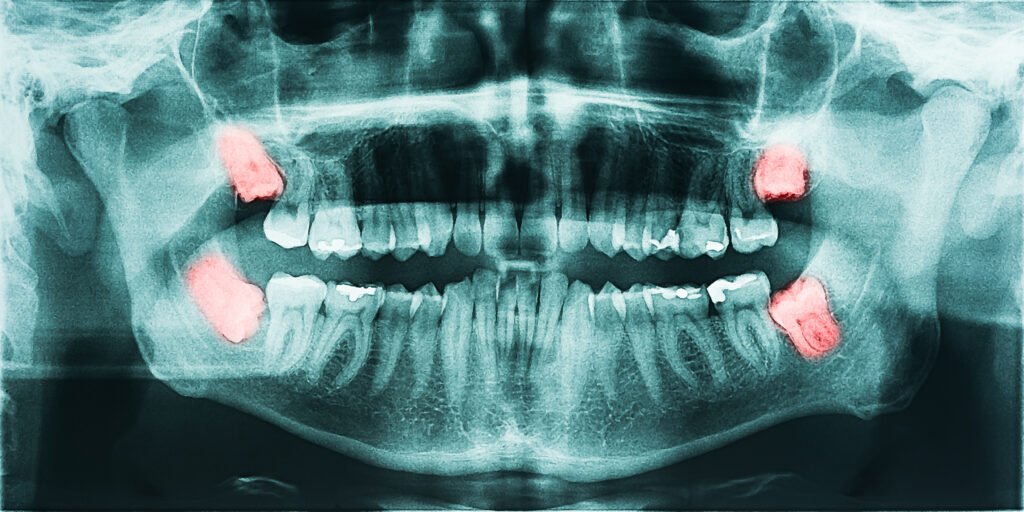

Extractions

Gentle, Safe Removal When a Tooth Can’t Be Saved

While preserving your natural teeth is always our priority, there are times when removing a tooth is the best option for your overall oral health. At Plaza Dental Care, we provide safe, comfortable tooth extractions using modern techniques and a patient-focused approach.

When is a Tooth Extraction Necessary?

A tooth may need to be removed if it is:

- Severely decayed or damaged

- Infected beyond repair

- Broken below the gum line

- Causing overcrowding

- Loosened due to advanced gum disease

- Impacted (such as wisdom teeth)

We always explore restorative options first before recommending extraction.